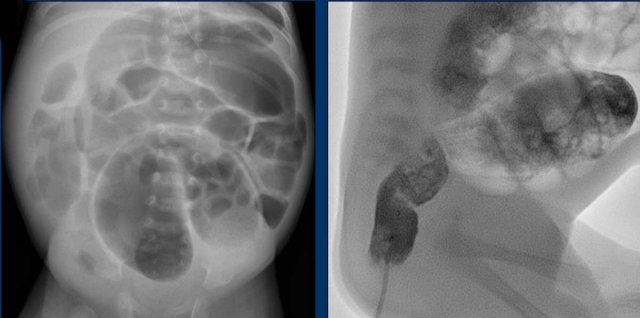

Images

Radiograph of a 2 month old baby with bilious vomiting after diaphragmatic hernia operation. There is very little bowel air consistent with the vomiting and collapsed bowel. On ultrasound ascites and a distended bowel loop with decreased perfusion are seen. In the mesentery a twist of the vessels is seen consistent with volvulus.